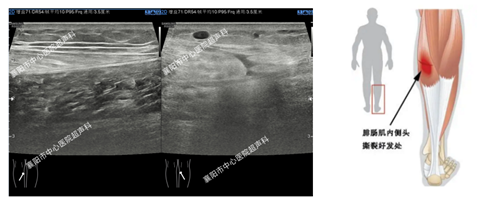

1、肌腱损伤的评估

(图中为跳绳损伤导致的小腿腓肠肌内侧头断裂)